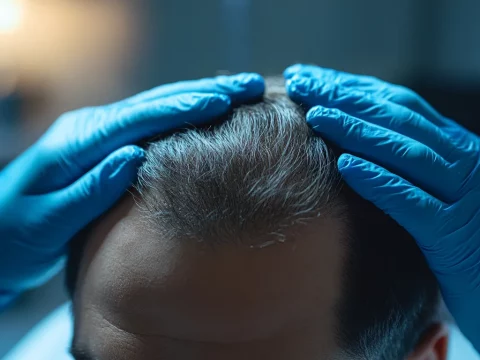

Ile kosztuje przeszczep włosów Turcja?

Przeszczep włosów stał się popularnym rozwiązaniem dla osób z problemem nadmiernego wypadania włosów oraz łysieniem….

Co to jest przeszczep włosów?

Przeszczep włosów to medyczna procedura, która polega na przeniesieniu włosów z jednego obszaru ciała do…